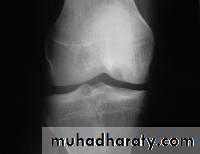

X-ray

The anteroposterior x-ray must be obtained with the patient standing and bearing weight; only in this way can small degrees of articular cartilage thinning be revealed.1-The tibio-femoral joint space is diminished

(often only in one compartment) and there is

2-subchondral sclerosis.

3-Osteophytes and

4- subchondral cysts

5-chondrocalcinosis are usually present and sometimes there is soft-tissue calcification in the suprapatellar region or in the joint

itself

X-ray Non weight bearing